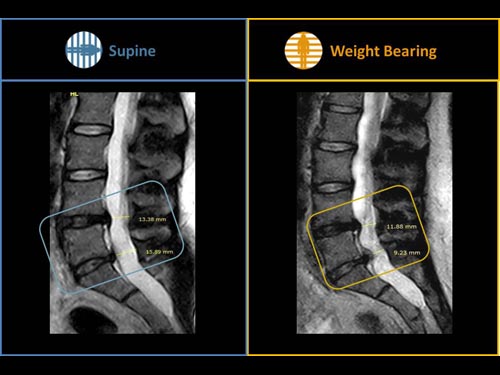

Nová končetinová magnetická rezonance G-scan Brio od společnosti Esaote je tomografický systém MRI, který umožňuje studium všech kloubů i páteře, ať už v klinostatické (vleže) nebo ortostatické (vážící) poloze, protože magnet i pacient se mohou otáčet od 0 do 90 stupňů. Díky inovativnímu designu G-scan mohou být pacienti Brio skenováni v poloze nesoucí váhu, aby se usnadnila diagnostika MSK u těch patologií, které se mohou měnit v důsledku držení těla a polohy, jako jsou bolesti dolní části zad.

• Další diagnostické schopnosti: jelikož gravitační síla generuje bio-mechanické změny v anatomii, MR zobrazení v přirozené poloze ve stoje vám umožňuje dosáhnout důležitých dalších informací ve srovnání s tradičními MRI